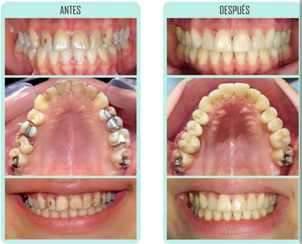

Paciente tratada por la Dra. Katherine Ruiz